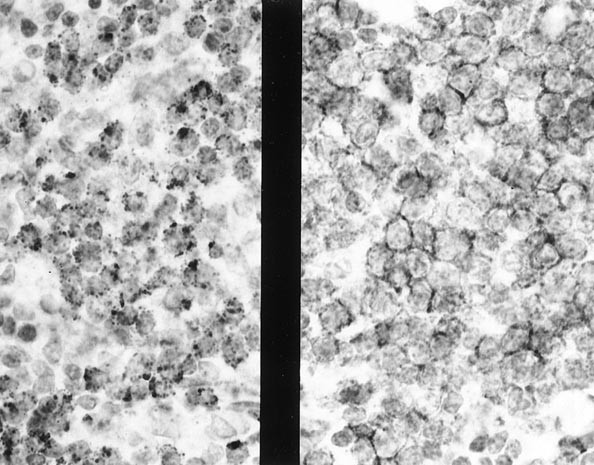

A nodular proliferation of atypical clear cells of intermediate size with abundant interspersed histiocytes was present in the malignant T-cells and infiltrated the breast parenchyma and fat (Figs. 3 and 4). The lymphoma seemed to follow the lobular breast architecture and the associated fibrosis accentuated in the striking nodularity. The axillary lymph node showed effacement of the architecture by the same infiltrate seen in the breast tissue. Numerous epithelioid histiocytes were seen throughout the malignant cells of the lymph node. Because of the numerous epithelioid histiocytes, the case initially was diagnosed as a peripheral T-cell lymphoma, lymphoepithelioid cell (“Lennert's” lymphoma); we reclassified the case as PTCL, medium cell. Immunohistochemical studies showed that the malignant cells were immunoreactive with CD45RB, CD3, CD45RO, βF1, CD43, CD8, and TIA-1. Rare cells were immunoreactive with CD30. CD56 was weakly immunoreactive in 20% of the cells. The cells were negative with CD20, CD4, TCR δ-1, and cytokeratin. CD20 highlighted sparse B cells, which were found at the periphery of the nodules in the breast. No evaluation for LE components could be made in the breast mass because the unstained slides were limited. The TCR γ assay showed a monoclonal band. The IgH assay and TCR β assays showed no monoclonal band.

The breast lobules and soft tissue were infiltrated with a malignant population of medium-sized lymphocytes with abundant clear cytoplasm (Figs. 5 and 6). The lobular infiltrate gave the appearance of LE lesions (Fig. 7). The cells in the bronchial biopsy had a similar appearance. No necrosis or vascular invasion was present. The malignant cells were immunoreactive with CD45RB (weak), CD3, CD43, TIA-1, and CD56 (Fig. 8). The cells were negative with CD20, CD45RO, βF1, TCR δ, CD30, CD4, CD8, latent membrane protein for Epstein-Barr virus, and cytokeratin. The diagnosis was revised to NK/T-cell lymphoma. No monoclonal band was found in the IgH or the TCR β or γ assay. The in situ hybridization study for Epstein-Barr virus–encoded RNA was negative.